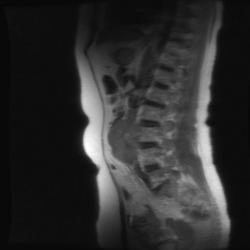

T2 ВИ Sagittal